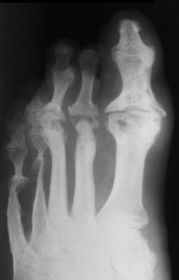

What disease is this? What is shown by A, B and C? | Psoriatic arthritis. A = destructive changes B = Pencil in cup deformity C = IPJ fusion |

What disease is this? | Psoriatic arthritis |